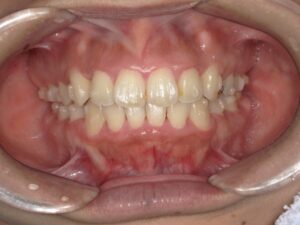

まだ、矯正治療中ですが現在の写真を以下に示します。

【現在の状態】

この患者様は、矯正診断時、骨格的な不調和が大きく手術を併用した矯正治療が必要だと診断されておりましたが、なんとか手術なしでできないかとご相談を頂き、可能なところまでやりましょうと矯正治療がスタートしました。